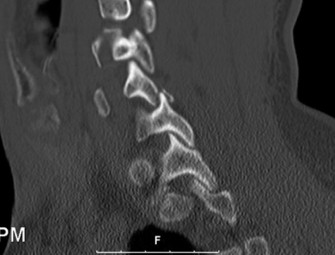

Radiographic and Computed Tomography Evaluation

Initial trauma radiographs demonstrated a loss of anterior and middle column height at L1, with a focal kyphotic deformity. However, plain films are vastly insufficient for definitive surgical planning in thoracolumbar trauma. A high-resolution, fine-cut Computed Tomography (CT) scan of the entire spine was obtained. The CT images confirmed an L1 burst fracture with severe comminution of the vertebral body. Sagittal and axial reconstructions revealed 50% canal compromise secondary to a large retropulsed bone fragment originating from the posterosuperior aspect of the L1 vertebral body. Furthermore, the CT demonstrated 25 degrees of segmental kyphosis measured from the superior endplate of T12 to the inferior endplate of L1.

A critical finding on the axial CT slices was a vertical, split fracture propagating through the L1 lamina. This is a highly significant morphological feature. A lamina fracture in the setting of a burst fracture with retropulsion strongly correlates with a dural tear and potential entrapment of the cauda equina nerve roots. When the vertebral body bursts posteriorly, the pedicles are driven outward, and the lamina fractures as the spinal canal attempts to expand to accommodate the retropulsed bone. If the dura is lacerated, nerve roots can herniate through the dural defect and become incarcerated in the laminar fracture site.

The final, critical step is rod contouring and reduction. To prevent future Adjacent Segment Degeneration, the titanium rods must be contoured to match the patient's ideal pelvic incidence and lumbar lordosis. The rods are seated into the proximal screws. Using reduction towers and careful cantilever forces, the rods are seated into the distal screws. This maneuver actively corrects the 25-degree kyphotic deformity, restoring normal sagittal alignment. The construct is cross-linked if necessary, and a robust posterolateral decortication and bone grafting (using local autograft from the laminectomy and allograft) is performed to ensure a solid arthrodesis.

Radiographic follow-up includes upright AP and lateral plain films before discharge to verify the maintenance of sagittal alignment and hardware integrity. The patient is discharged home or to acute inpatient rehabilitation depending on their functional mobility.

Long-term follow-up at 6 weeks, 3 months, 6 months, and 1 year will focus on assessing fusion mass consolidation and monitoring for any signs of hardware failure. More importantly, long-term surveillance (2 to 5 years post-op) will focus on the adjacent segments. By having meticulously restored the sagittal vertical axis (SVA) and regional lordosis during the index procedure, we have minimized the abnormal shear and compressive forces on the T10-T11 and L3-L4 discs, drastically reducing the patient's risk of developing Adjacent Segment Degeneration requiring revision surgery.